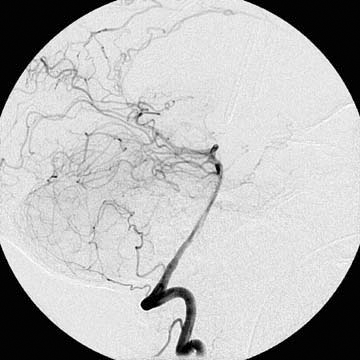

A diagnostic angiography was done during his hospitalization and yielded the following images.